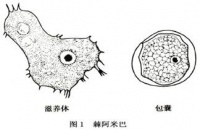

二、霉菌性角膜炎[编辑 | 编辑源代码]

霉菌性角膜炎发生的原因包括类固醇及免疫抑制剂的使用增加,还有角膜因为接触到树枝、植物或蔬菜而造成角膜创伤。通常病灶边缘不规则,会出现羽毛样的浸润,在严重感染时会产生一个完全不透明的角膜,亦可能发生坏死及穿孔。

前段时间发生疑似由某品牌隐形眼镜药水引起之霉菌性角膜炎,新加坡、香港等地甚至停止销售并回收该产品,然而什么是霉菌性角膜炎呢?

4inLOOK隐形眼镜专家指出,霉菌又称做真菌,存在水与土壤之中,尤其是台

湾温暖潮湿的气候环境,更有助于其生长。此外,霉菌的种类繁多,其中会对人体有害的约50种,例如镰胞菌及念珠菌等。

正确保养不可省

因此,角膜炎若是由霉菌引起则称之为霉菌性角膜炎,且由于霉菌外层有囊膜保护,比一般细菌更难杀死,如果眼睛万一受到感染,霉菌会快速繁殖且深入眼睛组织,并出现红眼、疼痛及视力模糊等症状,此时只能使用局部或口服的抗霉药物治疗,病情严重者甚至变成角膜溃疡、角膜穿孔,终致失明而须进行角膜移植手术。

4inLOOK隐形眼镜专家表示,霉菌性角膜炎很难医治,如果没有及早发现与治疗,可能会导致失明,所以隐形眼镜配戴者一定要选择杀菌力足够的保养液,并依照正确指示保养镜片,以免感染。